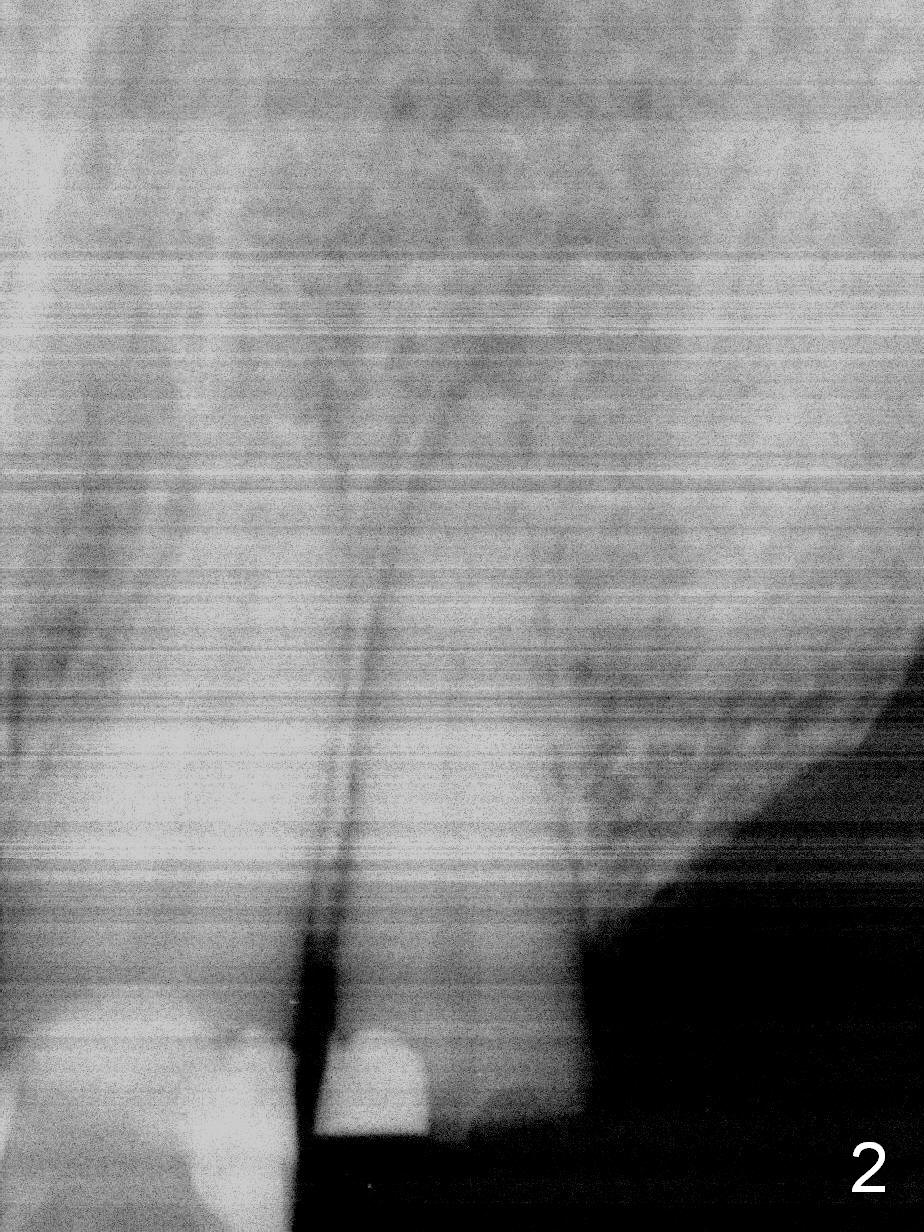

How to avoid apparent iatrogenic damage to the neighboring root? Preop PA shows approximation of these roots (Fig.2). Unfortunately the initial osteotomy is too mesial (Fig.3), which is unnoticed. When a 4.5x17 mm implant is placed, there is distal gap (Fig.4 <), while the mesial one is closed.